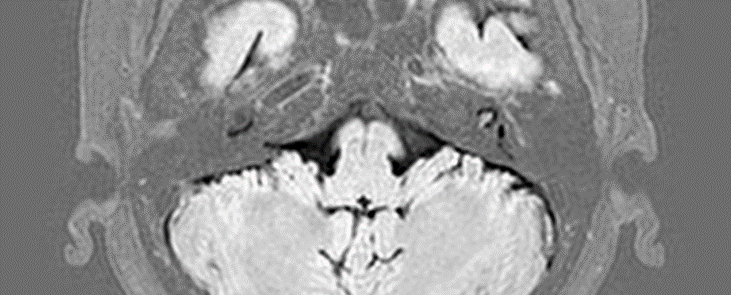

图为内耳轧造影显示病变部位

伊主任迅速为牛女士安排了内耳功能检查及影像学检查,影像学显示内耳膜迷路积水凭借丰富的临床经验和敏锐的洞察力,最终牛女士确诊为“耳石危象”,是梅尼埃病的一种特殊类型。梅尼埃病是一种由于内耳膜迷路积水积水导致的疾病,常常表现为反复发作的眩晕和波动性的听力下降,发作时还常常伴有耳鸣和耳闷堵感。梅尼埃病反复发作,不仅会影响日常行动和生活,这种突然发生眩晕的恐惧感还会令患者不敢外出,而耳石危象则为其一种特殊发作形式,患者会反复出现不明原因的跌倒发作,引发更为严重后果。